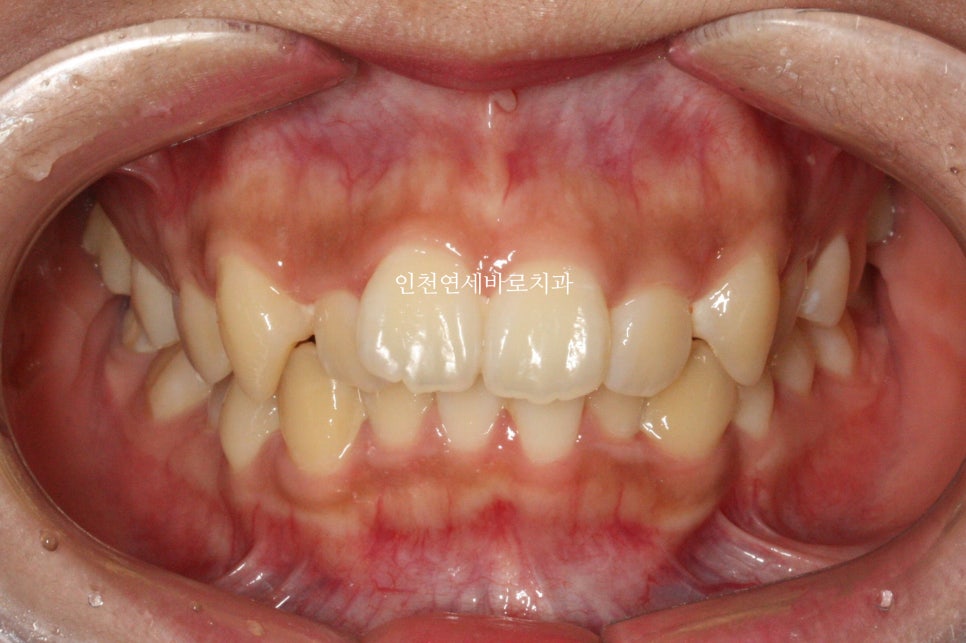

위아래 덧니가 있었고, 깊이 물리는 과개교합 및 중심선의 불일치 보이고 있습니다.

입술이 많이 들어가진 않았지만, 편안하게 다물어 지는 것이 보이죠?

중심선 및 교합 모두 잘 유지되고 있습니다.

긴밀한 교합과 배열로 잘 유지되고 있다고 판단됩니다.